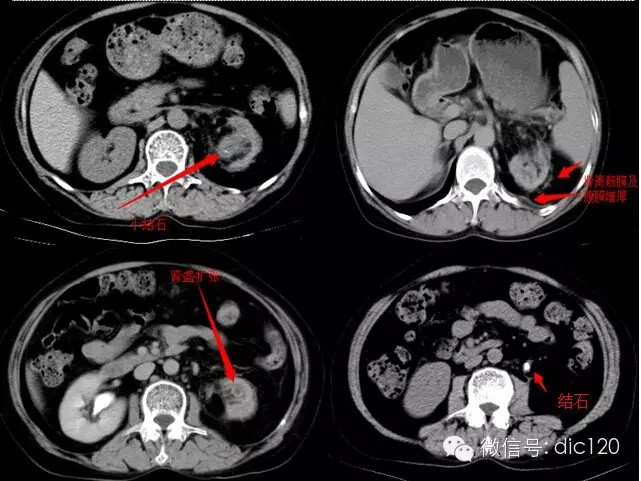

影像表现:CT平扫左肾体积变小,肾皮质变薄,肾盂扩张、壁增厚,见小点状高密度影,肾盏扩张,增强扫描病变周围组织呈环形强化,囊变区不强化,肾周模糊,筋膜增厚,临近腹膜增厚,左侧输尿管近段见结节状高密度结石影。 分析:1、中年妇女,左上腹不适;2、肾盂肾盏扩张、壁增厚,增强环形强化;3、输尿管及肾盂小结石;4、肾周筋膜增厚。 符合肾脏感染性病变,考虑黄色肉芽肿型肾盂肾炎。 |

| 疾病总结: | 黄色肉芽肿型肾盂肾炎是一种少见的肾实质慢性肉芽肿样炎性疾病,常见于中年妇女,临床上常表现为腰痛、发热、消瘦及脓尿等急慢性肾盂肾炎症状,约70%合并尿路结石,典型为鹿角样结石。CT表现:平扫时,常见肾盂内软组织肿块影,边缘多不清楚。累及肾实质表现为肾脏普遍增大,本例肾脏体积缩小,考虑慢性炎症所致,内有大小不一不规则低密度影,肾周筋膜增厚是本病的一个较特征性改变,同时也是鉴别肾肿瘤的一个重要鉴别点;增强扫描病变周围组织呈环形强化,囊变区不强化,囊变区,可多发或单发,囊变区为扩张的肾盏,坏死组织为黄色瘤样组织。肾功能较差。 |